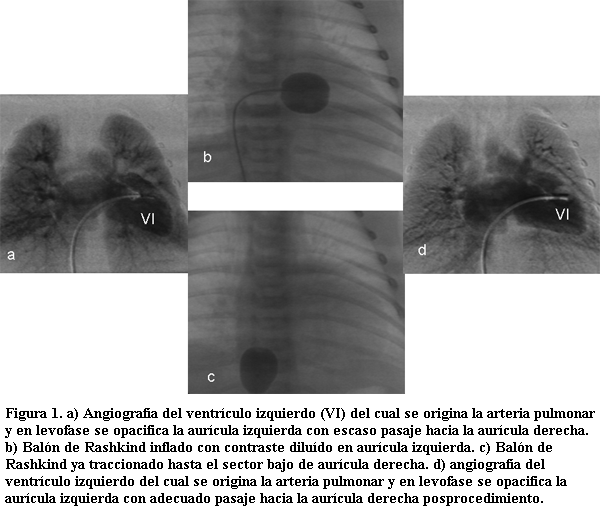

En estas situaciones, la solución quirúrgica muchas veces se ve comprometida por tratarse de postoperatorios de cirugía cardíaca en donde el procedimiento de disección para acceder al vaso afectado suele ser muy dificultoso. Es así que el poder realizar un procedimiento de recanalización de vasos por intermedio de catéteres adquiere jerarquía. Recientemente se ha descrito una nueva técnica utilizando la radiofrecuencia en la cual con una variación de las características de las ondas de radiofrecuencia utilizada para la ablación de focos productores de arritmias, (con bajo voltaje y alta temperatura) se logra perforar estructuras y a partir de allí mediante dilataciones progresivas darle al vaso un diámetro adecuado, incluso con la utilización de stents (figura 3).